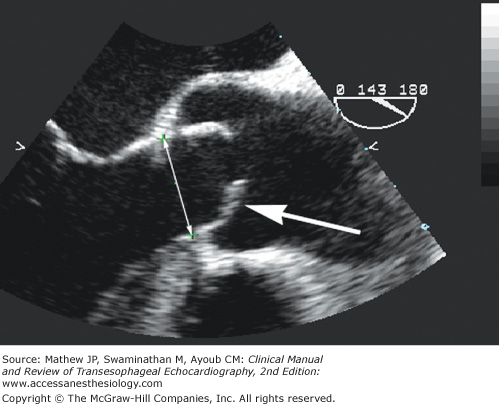

Figure 9-4.

Midesophageal aortic valve long-axis view during systole demonstrating the characteristic doming of a stenotic bicuspid aortic valve with pliable leaflets (arrow). Planimetry can overestimate aortic valve area in this patient if the ultrasound beam does not intersect the leaflet tips. The annulus diameter is measured from the hinge point of one leaflet to the hinge point of the opposing leaflet during systole.